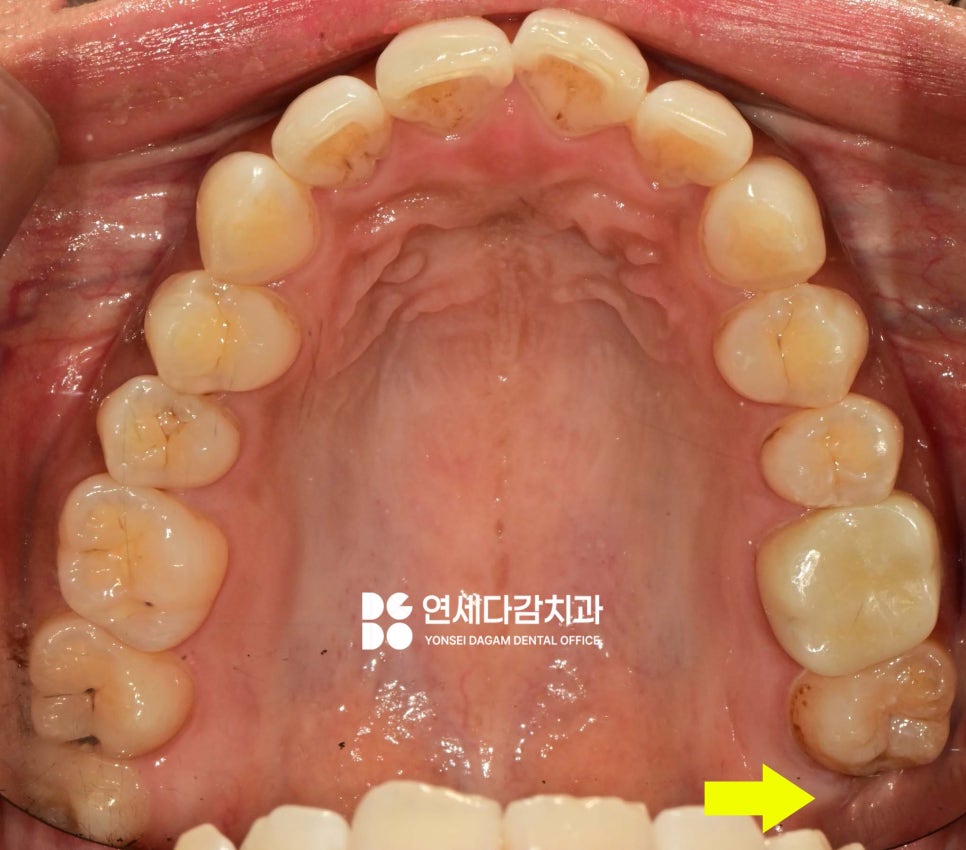

해당 케이스는 사랑니 주변으로

잇몸이 부어서 통증을 호소하고 있었습니다.

오래전부터 문제가 있다는 것을

인지하고 있었으나,

공포감이 심해 그동안 계속

치료를 미루고 있었습니다.

구강 검사 결과,

아래 매복 사랑니 주변으로

특히 심한 부종이 관찰되었으며,

해당 부위를 촉진했을 때

고름이 나오기도 했습니다.

이는 감염(지치주위염)이 진행 중임을

나타내는 명백한 징후였습니다.

추가로 위쪽 사랑니 부위에도

음식물이 자주 끼고,

평소 위생관리에 어려움을 겪고 있었습니다.

또한 어금니 중 하나는

심한 인접면 충치가 발견되었습니다.

충치가 치수(신경)에 도달한 것은 아니었으나,

범위가 넓게 퍼져있어

그 부위를 모두 제거하면 치관의

상당 부분이 사라지게 됩니다.

따라서 레진 코어를 통해

치관 구조를 재건한 뒤 크라운을 씌워

보호하는 것이 좋다고 판단되었습니다.